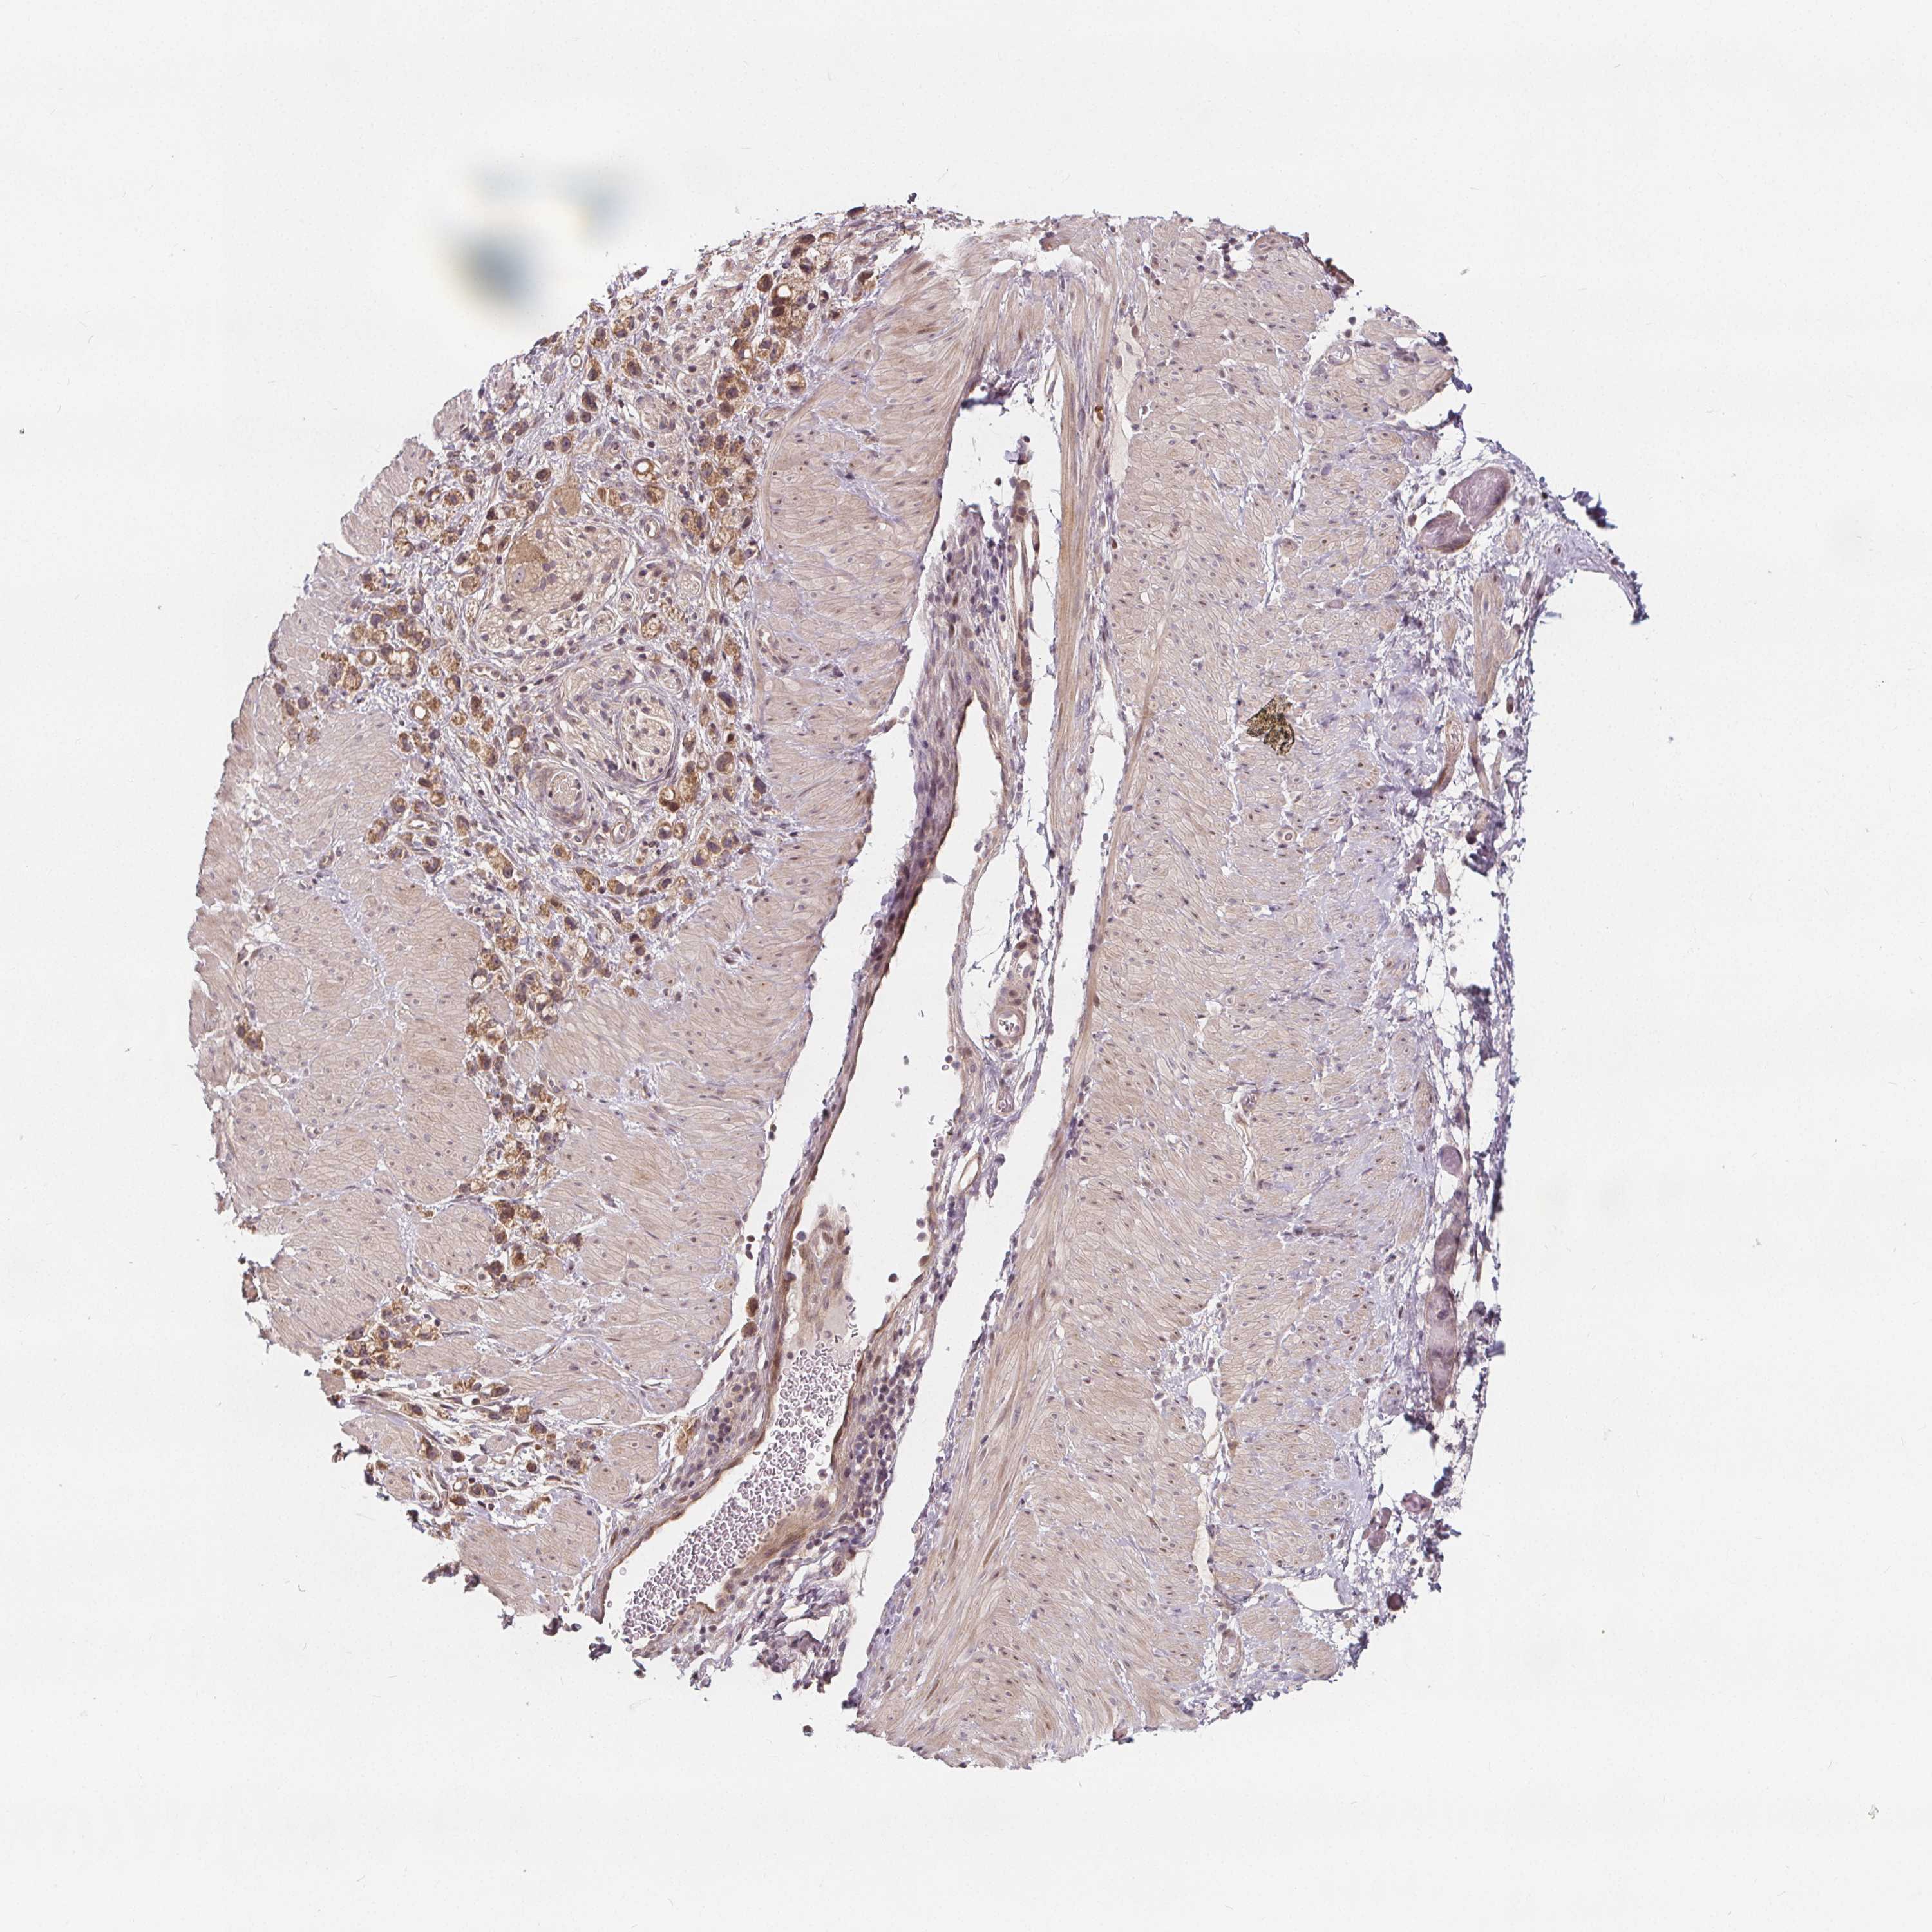

STOMACH CANCER - Protein expressioni

A mouse-over function shows sample information and annotation data. Click on an image to view it in a full screen mode. Samples can be filtered based on level of antibody staining by selecting one or several of the following categories: high, medium, low and not detected. The assay and annotation is described here.

Note that samples used for immunohistochemistry by the Human Protein Atlas do not correspond to samples in the TCGA dataset.

Antibody stainingi

Antibody staining in the annotated cell types in the current human tissue is reported as not detected, low, medium, or high, based on conventional immunohistochemistry profiling in selected tissues. This score is based on the combination of the staining intensity and fraction of stained cells.

Each image is clickable and will lead to virtual microscopy that enables deeper exploration of all samples and also displays staining intensity scores, fraction scores and subcellular localization as well as patient and tissue information for each sample.

Antibody HPA064427

Antibody HPA075510

Antibody CAB021903

Staining

Adenocarcinoma, NOS

Adenocarcinoma, High grade